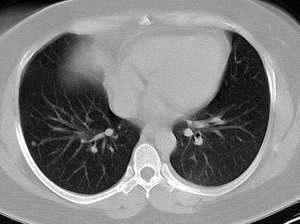

以下是引用wawaquan在2006-2-4 13:32:00的发言:[br]双上叶后段及右下叶多发大小不等圆形高密度影,与血管影相连;左下叶背段呈软组织密度影,边缘膨突,其内见一点状气体密度影,邻近胸膜增厚;纵隔淋巴结不大。[br] 女性,32岁,正哺乳期。近一周发热咳嗽,今晨咳血一次。 [br] 考虑:①双上叶后段及右下叶多发转移瘤,建议查盆腔排除子宫滋养叶细胞肿瘤。[br]②左下叶背段阻塞性炎症可能大。